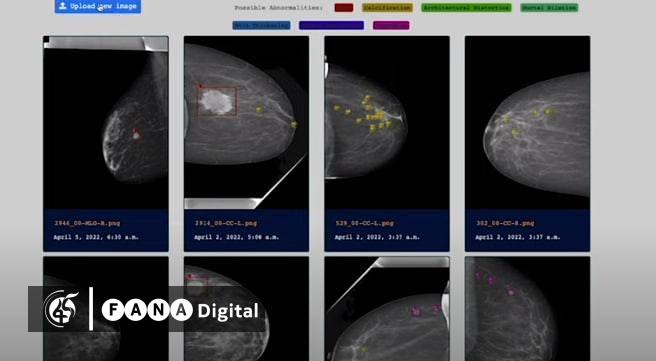

ሆኖም ይህ ሞዴል ምስሉ ከተገኘ በኋላ ካንሰሩ ያለበትን ቦታ ለይቶ እና ደረጃውንም ለይቶ ያለውን ውጤት እንደሚያወጣም ከኢንሰቲትዩቱ ያገኘነው መረጃ ያመላክታል፡፡

ይህም ከጊዜ አንጻር ያለው ጠቀሜታ ከፍ ያለ መሆኑ የተገለጸ ሲሆን ፥ ድካምን በማስቀረትም አስተዋጽዖ እንዳለው ተገልጿል፡፡

በኢትዮጵያ ካለው የዘርፉ ባለሙያዎች እጥረት ጋር ተያይዞ እንዲሁም የታካሚው ቁጥር መጨመር በሚታይበት ወቅት የቴክኖሎጂ ሞዴሉ በሽታው ያለበትን ሁኔታ ለማወቅ ከፍተኛ ጠቀሜታ እንዳለውም ነው የተነገረው፡፡